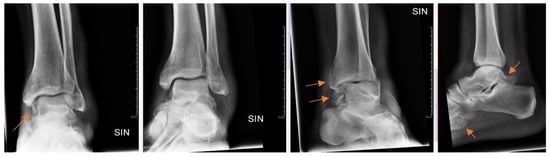

Radiology specialists interpreted more radiographs as having subtle findings compared to residents (p = 0.04). Different age groups did not differ (p = 0.89) between subtle or obvious cases. Radiology specialists missed correct diagnoses in subtle and obvious radiographs in 33% and 4.9%, respectively. In contrast, residents missed correct diagnoses in subtle (Figure 2) and obvious (Figure 3) radiographs in 51% and 8.4%, respectively.

Figure 3.

Patient with ankle trauma. Multiple obvious findings (arrows) in radiographs that were all missed by the resident.

From all the missed findings in the radiographs, 70% (n = 44) were interpreted as having an impact on patient care (p = 0.02), but this did not differ between the radiology specialists and the residents. Findings missed by the radiology specialists (Figure 4 and Figure 5) affected patient care in 71% of cases and overcalls in 31% of cases. Findings missed by the residents (Figure 6) affected patient care in 69% of cases and overcalls in 47% of cases. From all the overcalls in the radiographs, 40% (n = 12) seemed to have an impact on patient care. The most common impact on patient care was a lack of the necessary control study (40%), followed by an unnecessary control study (14%). Interpretation error rarely led to unnecessary operative treatment (1%).